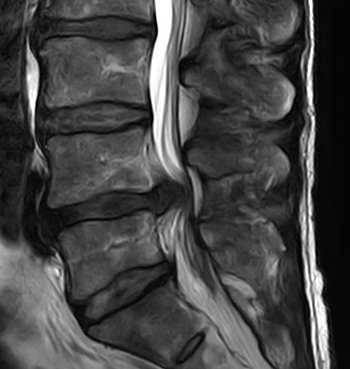

Spinale Neurochirurgie

Wirbelsäulenchirurgie

Bandscheibenvorfall

Spinalkanalstenose

Wirbelgleiten